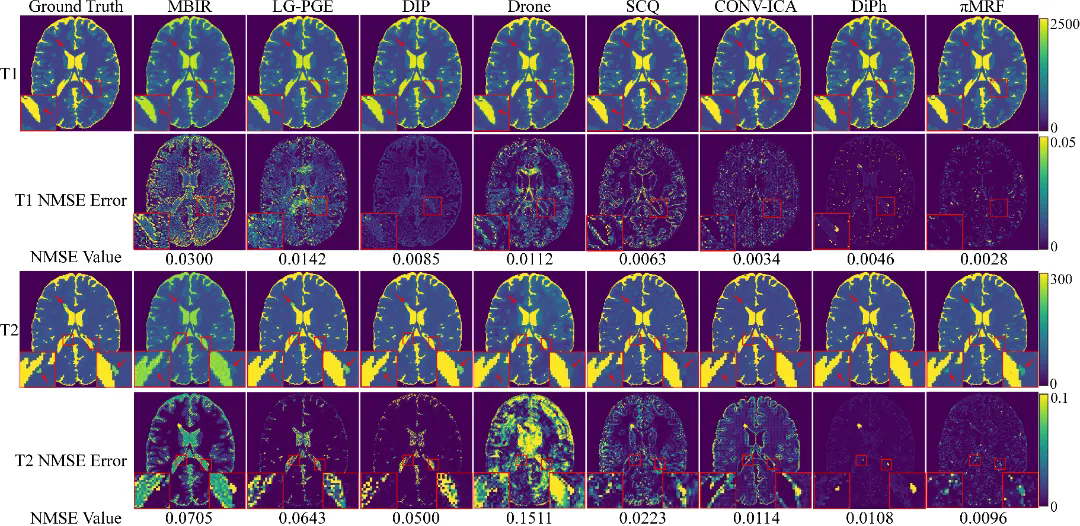

在数字仿真、水模仿体以及在体人脑实验中,πMRF在极端欠采样条件下均表现出更高的定量准确性与空间一致性,能够稳定恢复T1、T2和PD参数分布,并在组织边界及病灶区域保持更可靠的细节表达,整体性能显著优于现有对比方法。上述结果表明,该研究有效缓解了 MRF 在极端欠采样条件下面临的不适定逆问题,展示了“物理模型与陆续在神经表示深度融合”在复杂医学成像反演任务中的应用潜力。

图5:在体人脑实验结果